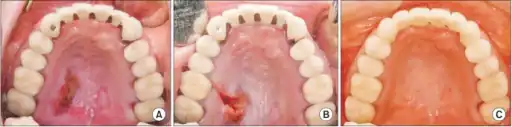

Initially, the lesion is a tender, erythematous (red) swelling. Later, in the ulcerated stage, the overlying mucosa breaks down to leave a deep, well-circumscribed ulcer which is yellow-gray in color and has a lobular base.[1]